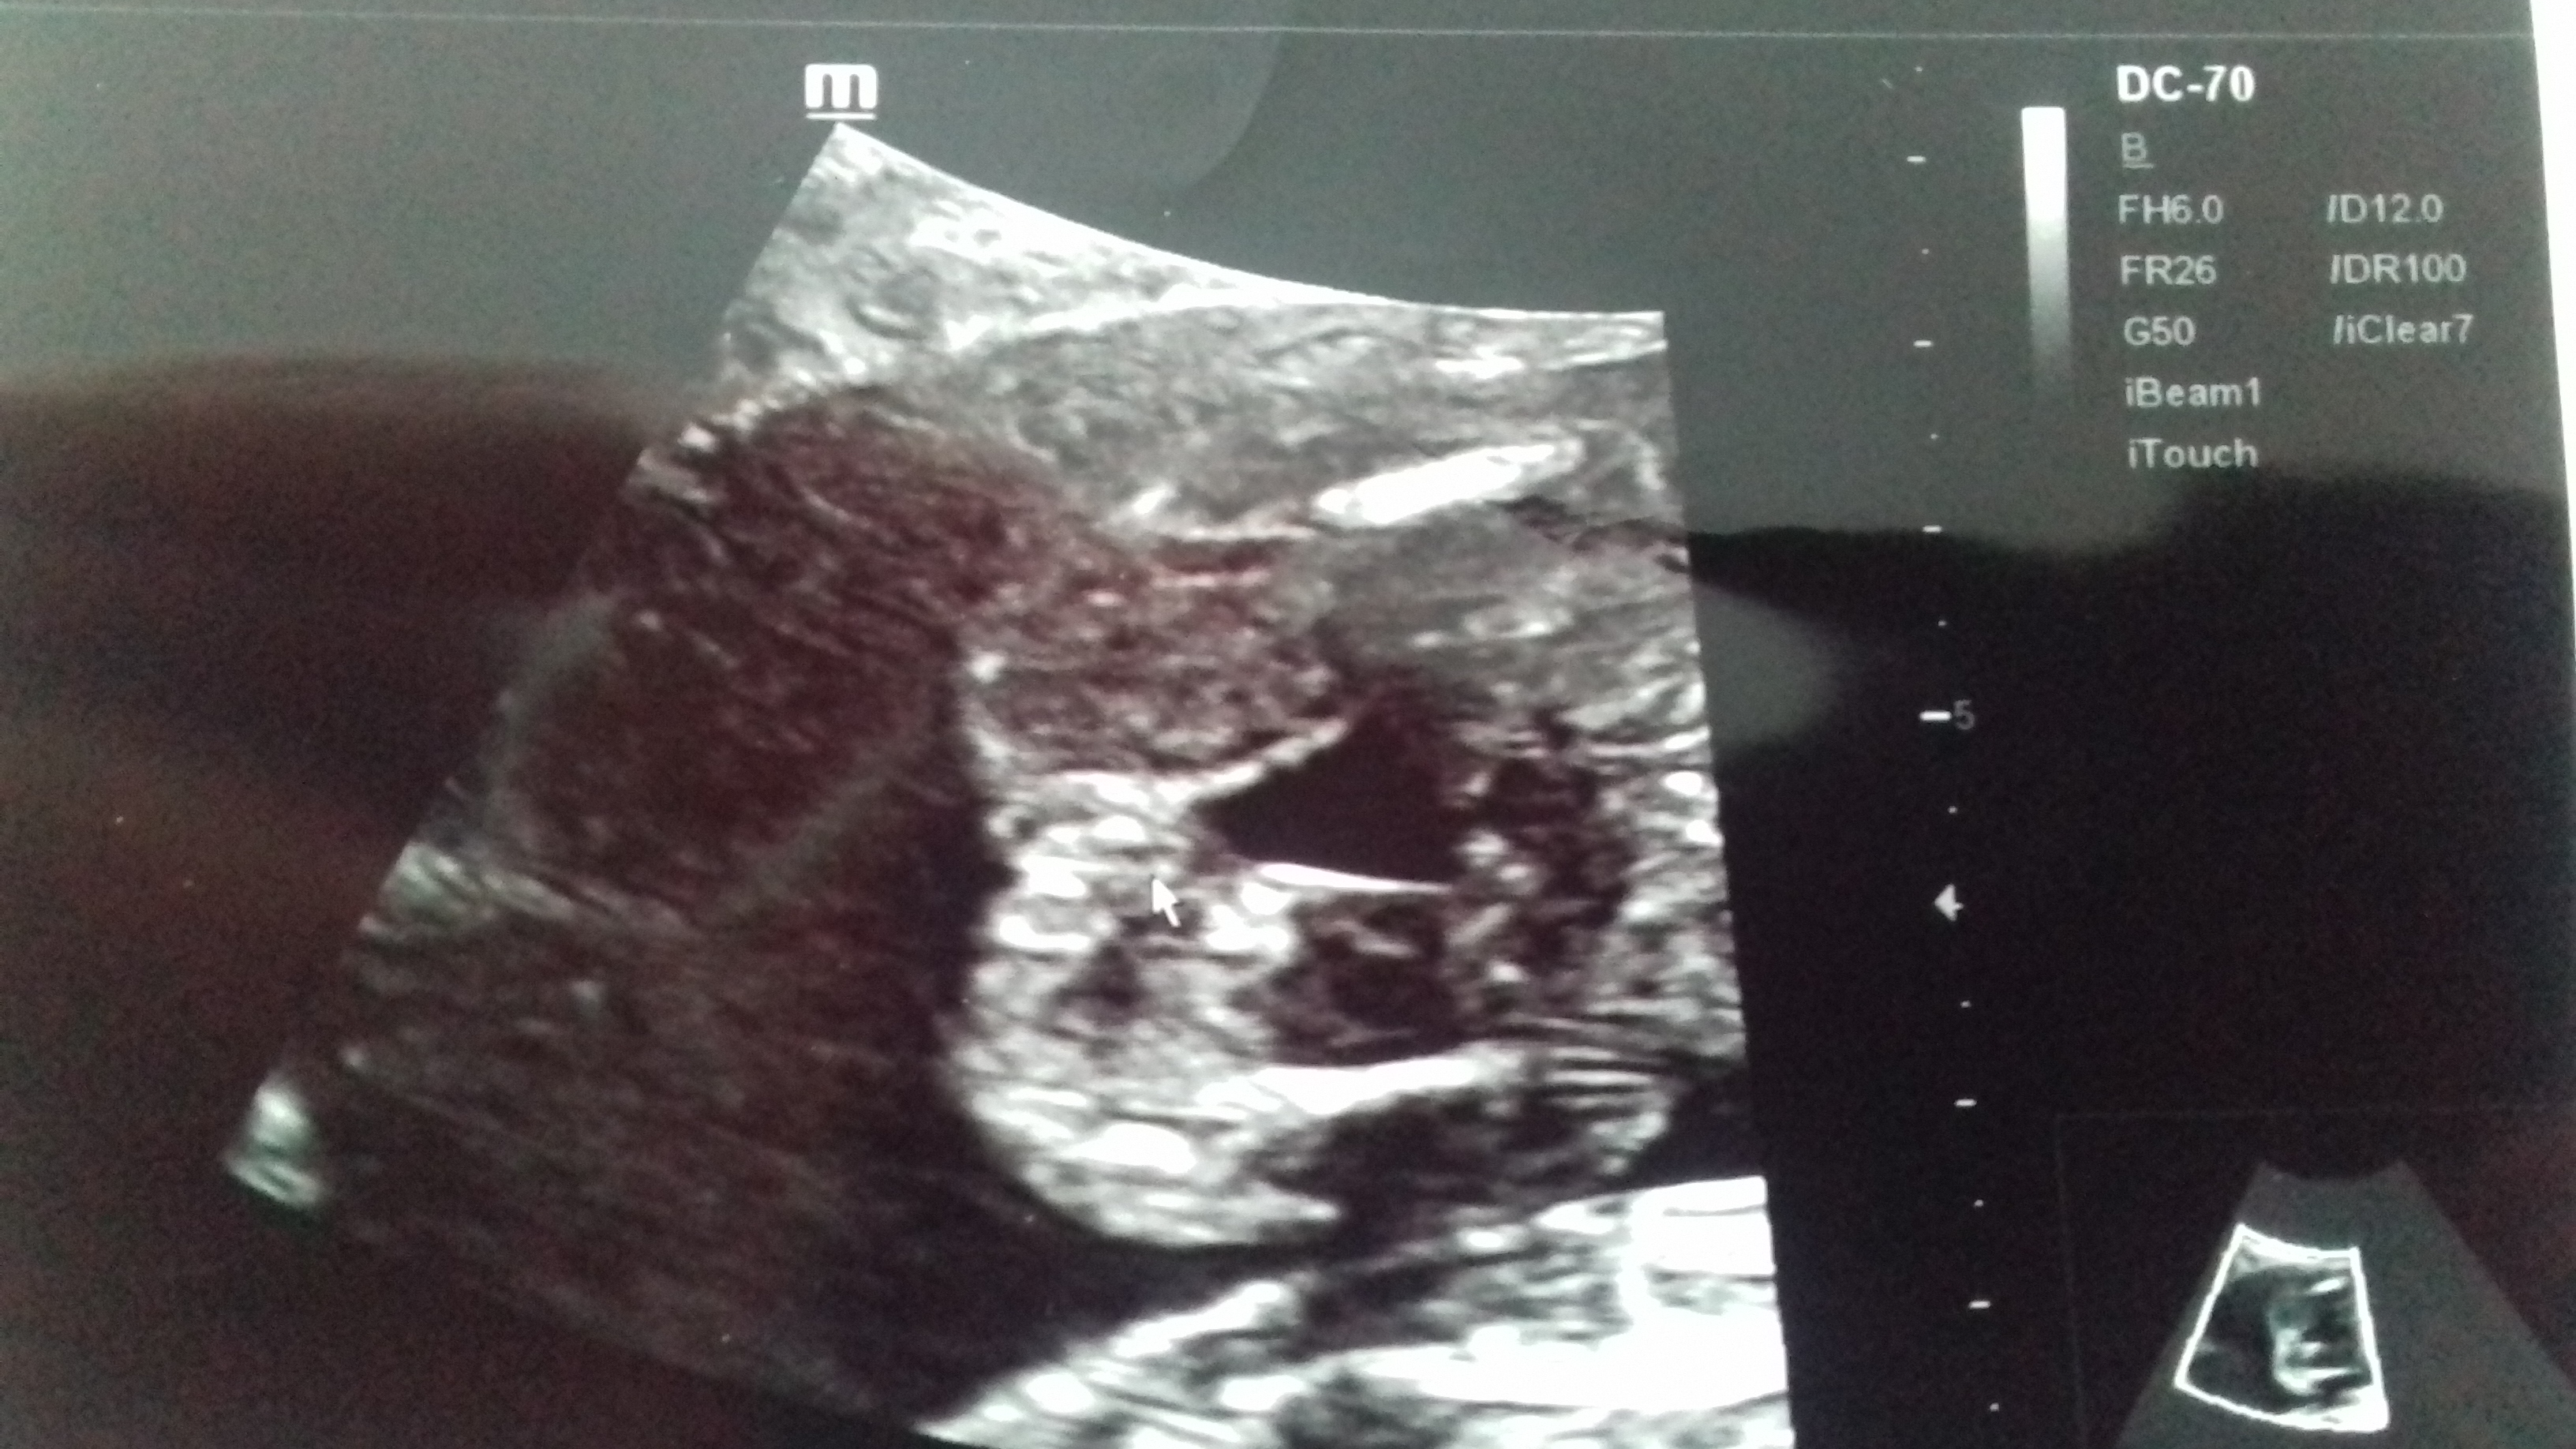

nedá mi to, abych si tu neudělala takovou malou "anketku". Co vidíte na obrázku u šipky? :-) Předem díky za vaše názory!

Díky moc, vypadá to jednoznačně. Doktor taky zmínil holčičku, ale mlžil, znáte to, holčička je vždycky nejistá...